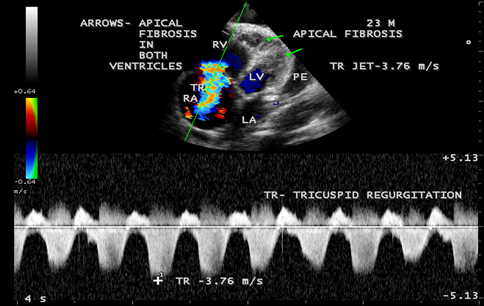

Figure 11: Apical four chamber view suggesting RV (right ventricular) apical fibrosis, RA dilatation and severe tricuspid regurgitation suggesting right ventricular endomyocardial fibrosis with an extension of fibrosis in the LV apex

Figure 12: Apical four chamber view showing the RV apical fibrosis with mild pericardial effusion in a 23-year old male with tuberculosis.

Figure 13: CW (continuous wave Doppler) showing the tricuspid jet velocity 3.76 m/s with Pulmonary artery systolic pressure of 67 mmHg ((4 x 3.76 m/s)2 + RA pressure (10 mmHg), suggesting pulmonary hypertension due to coexisting lung disease (tuberculosis) in RV EMF with fibrosis extending to LV apex.

A 52-year old male was admitted with symptoms of cough and breathlessness for 6 months duration. He had sudden onset of itchy skin lesions on the trunk and extremities for one-month duration following the respiratory infection. Blood chemistry, ECG and X-ray chest were normal. Serum ASO (anti-streptolysin O) titer was negative. Physical examination revealed numerous, itchy, drop-shaped small salmon-pink papules, 1-10 mm in diameter, scaly and covered with silvery-white ‘micaceous scales’, predominantly seen on the trunk and limbs as shown in Figures 1 and 2, suggesting the “Guttate Psoriasis”. It appears suddenly, 2-3 weeks after an episode of upper respiratory infection caused by group A beta- hemolytic streptococcal infection. On scratching, pinpoint bleeding occurs when the scales are removed (Auspitz’s sign) and the lesio ns induced by trauma to the skin (Koebner phenomenon). It is an immune-mediated inflammatory disease that causes an incre ase in epidermal cell turnover with hyperproliferation of keratinocytes. The environmental, genetic and immunological factors play a role in its pathogenesis.